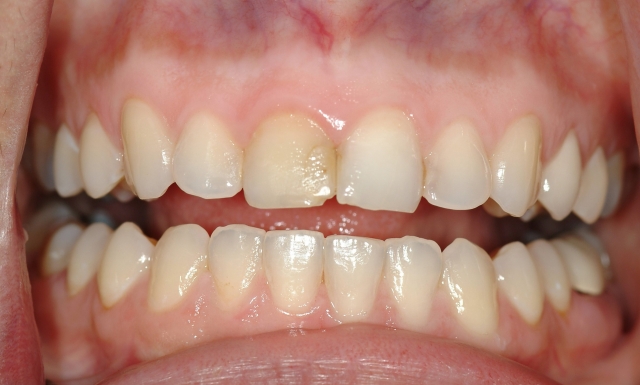

Recently in your practice, it’s very likely that you have: efficiently temporized a broken tooth and reassured a patient that it will be just fine; started endodontic therapy for a patient in acute pain and helped her sleep again; and placed composite on a chipped or broken front tooth and helped the patient smile again. (Figs. 1–3)